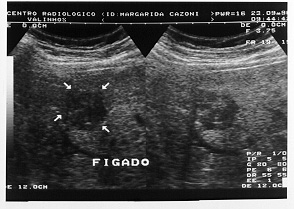

No pós-operatório foi submetida a radioterapia adjuvante no retroperitôneo. Evoluiu bem, sem evidência de recidiva durante o segmento ambulatorial até setembro de 1996, quando o ultrassom abdominal mostrou metástase hepática isolada (imagem 3), confirmada pela Tomografia computadorizada.

Foi submetida a nova laparotomia com ressecção da metástase de 3,5 x 4 cm, localizada entre os segmentos 5 e 6 hepáticos. O AP confirmou o diagnóstico de leiomiossarcoma metastático com margens livres.